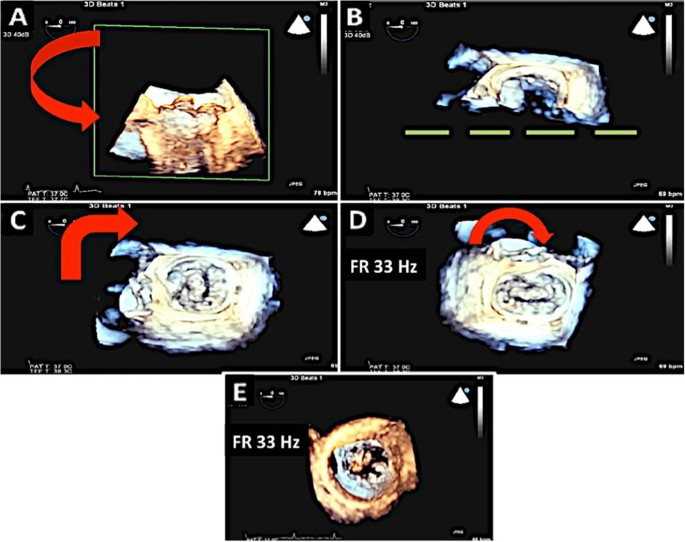

Steps taken in 3D acquisition of mitral valve. A: The image sector is focused on the mitral valve. Note that a one beat full volume acquisition has been performed. B: The image is then rotated towards the viewer. Once part of the mitral annulus is in view, the green plane is extended so that the entire mitral annulus can be viewed. C, D: The image is then rotated to position the aortic valve at the 12 o clock position. Here the mitral valve is seen from the left atrial side. E: The image can also be rotated so as to visualize the mitral valve from the LV side. This view can be useful to identify mitral clefts.